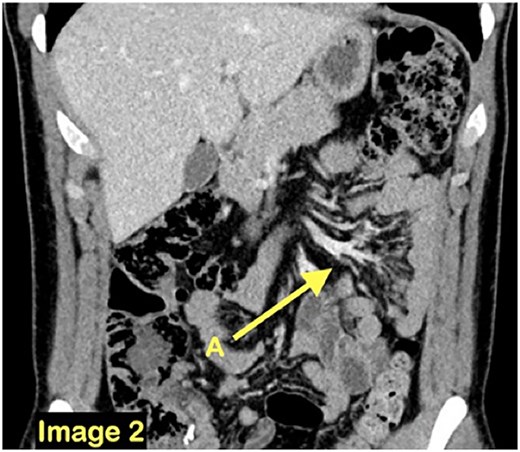

A coronal CT scan view demonstrating a cluster of small bowel loops (A) in the left abdomen.